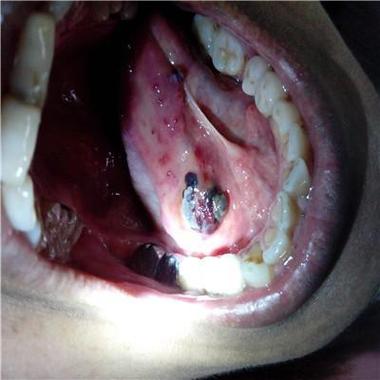

口腔毛细血管充血图片,预示哪些健康问题?

口腔毛细血管充血的典型视觉描述

口腔毛细血管充血,在医学上通常表现为黏膜发红,具体的样子取决于充血的严重程度和原因:

- 外观:

- 弥漫性潮红:大片的黏膜区域均匀地变红,像被刷了一层红色油漆。

- 点状或条状出血:在红色的背景上,可以看到针尖大小的红色或紫色小点(瘀点),或者细长的线条状出血(瘀斑),这些是毛细血管破裂出血的表现。

- 牙龈肿胀:牙龈不仅红肿,而且看起来肥大,质地松软,一碰就容易出血。